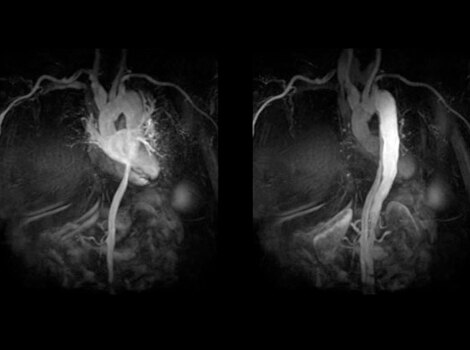

Pre-Procedure Planning

If considering catheter ablation as a treatment option, pre-procedure planning can involve use of MR or CT imaging to identify anatomical targets for the procedure and understand the extent of AF. These images can help guide decisions on necessity of left atrial appendage closure in certain populations.3

3D Heart

Visualize the anatomical structures and vascularity of the heart with a bright blood, 3D sequence.

Read More

After an ablation, regular patient follow up and non-invasive imaging assessment may detect potential return of Atrial Fibrillation.3

Visualize the anatomical structures and vascularity of the heart with a bright blood, 3D sequence. Read More